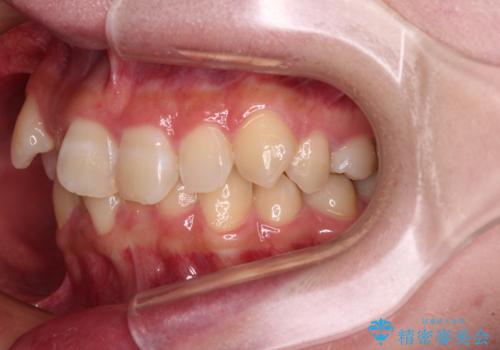

- 上下の八重歯を気にして来院された患者様です。

非抜歯矯正で歯列を整えると、治療後に口元が今よりも突出する可能性が高かったため、上下左右の小臼歯4本を抜歯し、ワイヤー装置にて矯正治療を行うこととしました。

右上の八重歯の影響で、右側は上顎歯列が前方位の咬み合わせとなってしまっていたため、上顎は第一小臼歯を、下顎は第二小臼歯を抜歯することで咬み合わせや上下正中を調整することとしました。

第二小臼歯抜歯の治療となったため、やや時間はかかりましたが、概ね予想通りの期間で治療を終えることができました。